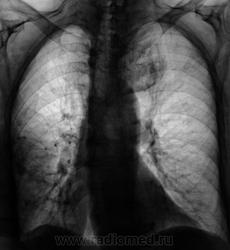

Мое мнение: слева в верхушке очаг затемнения - пневмонический фокус или туберкулема. Справа в нижних отделах - плеврокостальный выпот на фоне крупного кальцината. Ломит во всем теле - интоксикация. Думаю больше данных за пневмонию.

Синее - явно кость (аномалия ребра и т.п.). Желтое - самое подозрительное место, но без бока не привык всерьез оценивать такие затемнения. Розовая - неопределенная тень на фоне артефактного (?) снижения прозрачности. Там еще кальцинаты, но пока (до бока) не о них. Так что - бок, а лучше два))))

Круглые тени справа внизу могут быть метастазами.

Фрагмент с кальцинатами...

А,кстати,не тень ли это больной молочной железы?

уж больно сильно выделялась тень правой молочной железы да и кальцинаты свидетельствуют об мастопатии на фоне которой развился рак. + интуиция сработала.

судя по фото в натуре - рак раком.

На передней грудной стенке, от шеи книзу множество (на коже) "отверстий".

гражданочка вспоминает, что лет 15-20 тому, то были свищи, из которых обильно сочилось...